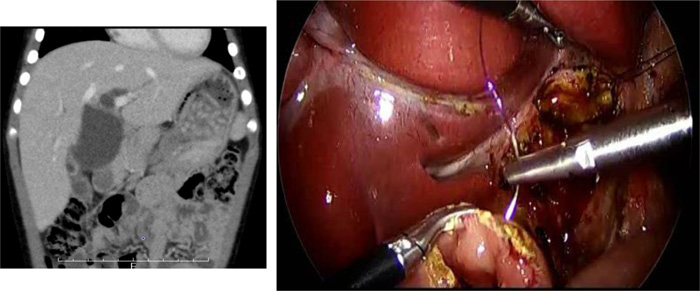

後腹膜鏡下腎盂形成術

・鏡視下腎盂形成術において、後腹膜アプローチは腹腔内操作がないため腹部内臓器関連合併症を回避できる

・従来の後腹膜開放の術式と同じ視野で同じクオリティーを保つこと ができ、開放手術へ変更を必要としたとき体位変換を行うことなくへ変更が可能

・体格の小さい乳児症例や癒着の危惧される再手術症例においても、工夫を加えることにより後腹膜鏡下で確実に安全に施行できる

・馬蹄腎合併症例の腎盂形成術でも従来の開放手術と同様に後腹膜アプローチで視野確保、吻合操作が可能である

後腹膜鏡下手術の実際

オリエンテーション

開放手術での経験と同じであり、創直下に直接腎へと到達できオリエンテーションが困難となることは少ない

術野スペース

手技的にUPJ周囲の剥離操作と同部位での吻合操作の みであり、運針の可能なスペースの確保のため開放手術 より少ない剥離範囲で手術可能となる利点がある

アルノート®ラップシングルを使用することで体格の小さ い症例でも鉗子操作スペースの確保ができる